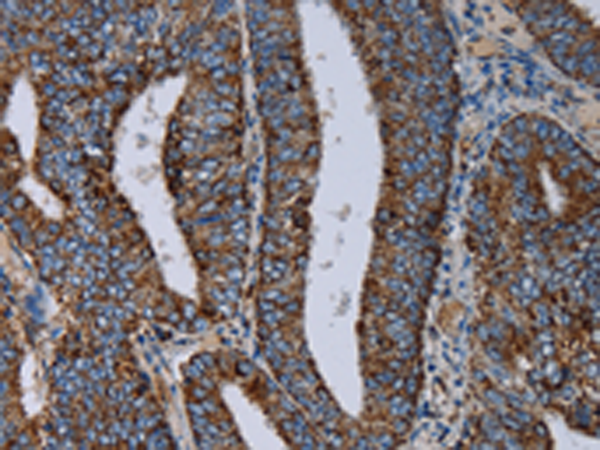

分类: 科研抗体货号: P08558别名: CI-13kA; CI13KDA; CI-13kD-A应用: IHC反应种属: Human, Mouse, Rat